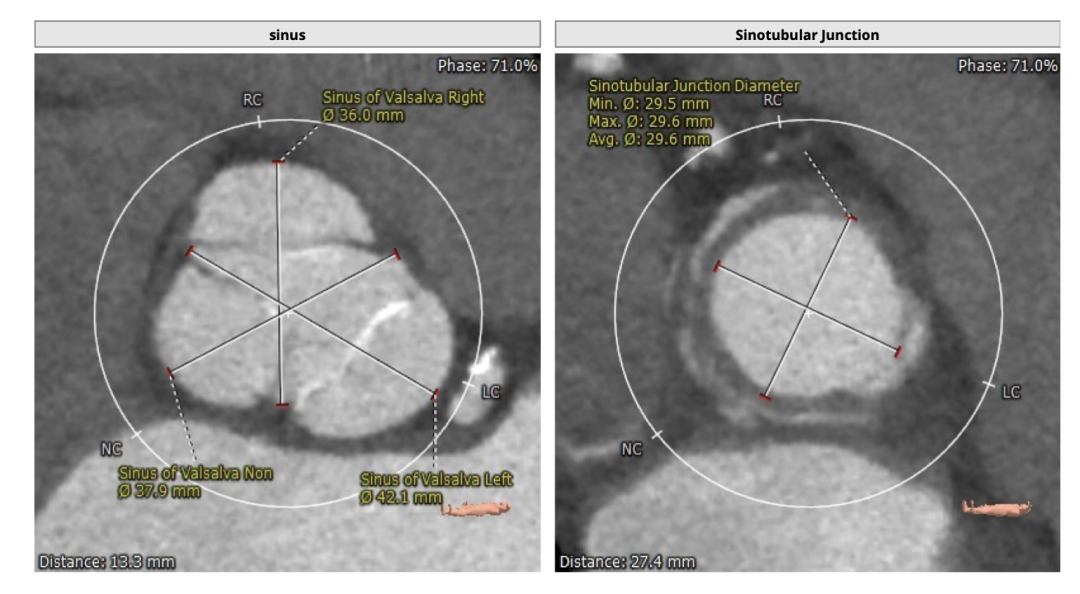

瓣环直径:30.5mm,左室流出道直径:30.3mm

主动脉窦:36.0*37.9*42.1mm,STJ:29.6mm